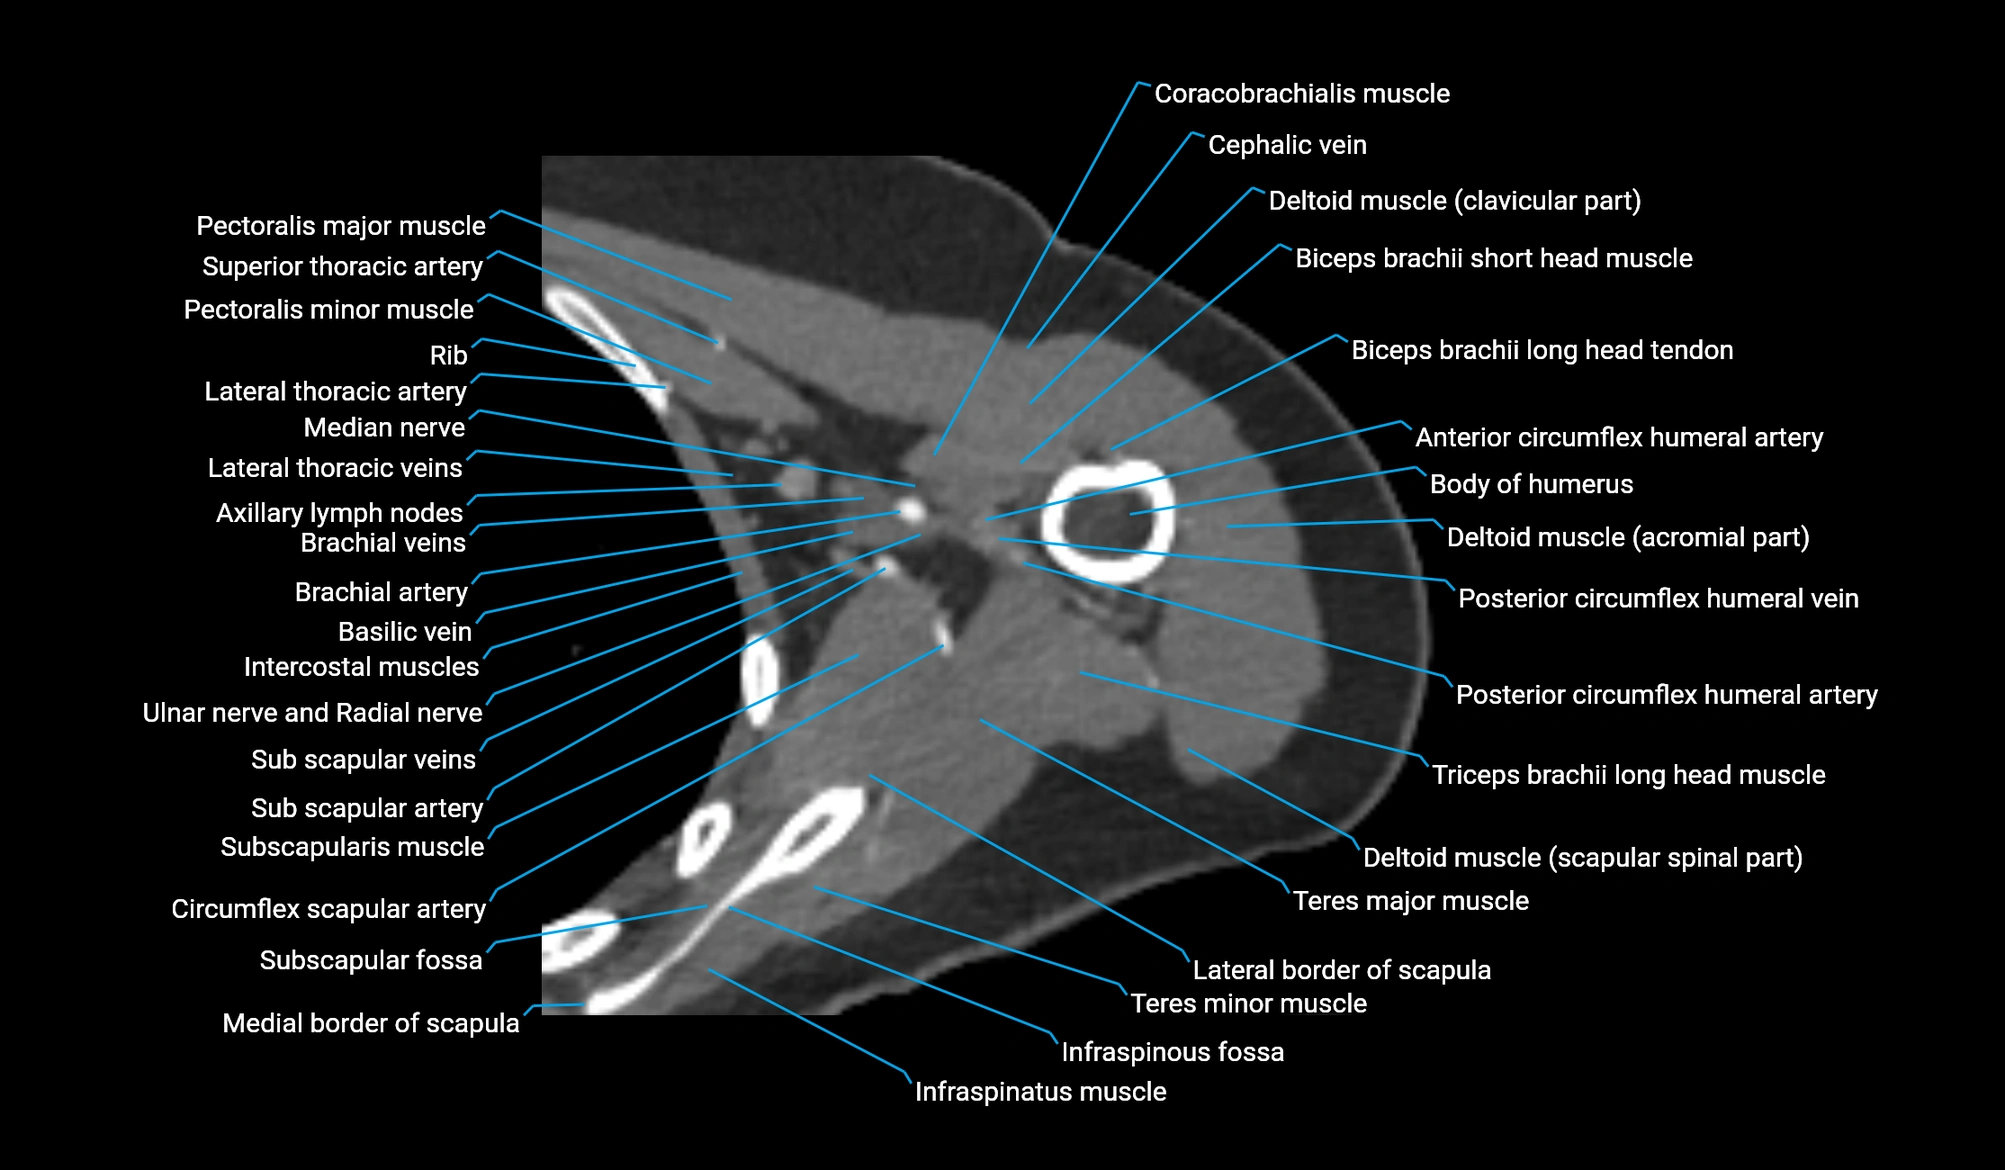

CT image